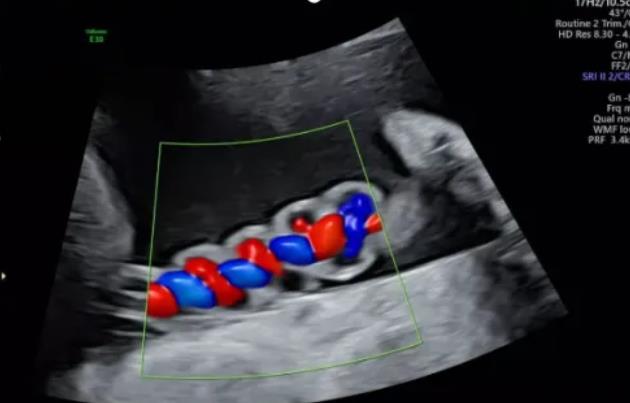

漯河市中醫(yī)院健康科普:超聲檢查之臍帶螺旋

聲像圖特征:臍動脈表現(xiàn)為過度螺旋,臍血管變細,縱切面呈“麻花狀”,橫切面呈“鼠眼狀”;

2、臍帶螺旋過松

聲像圖特征:胎兒臍帶縱切面示血管呈平行排列,螺旋稀少,彩色多普勒血流成像示臍帶血管內(nèi)充滿的紅藍血流呈平行排列,麻花狀螺旋消失。